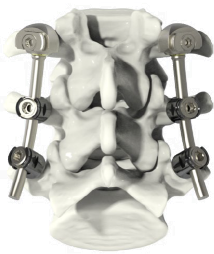

NONNWEILER, GERMANY, February 9, 2026 /EINPresswire.com/ -- In January, the first MOVE®-P implantation was performed in Hamburg by Dr. Ardeshir Ardeshiri. MOVE®-P is a pedicle screw based physiological motion preserving device to top-off a fusion. MOVE®-P is the result of an intensive multi-disciplinary product development with unprecedented biomechanical testing. The implantation was performed in the context of a multi-center feasibility trial in Germany.

"I am excited to be part of this feasibility trial and implanting the first MOVE®-P ever. MOVE-P works like an internal brace, supporting physiological motion in the adjacent level to a fusion. The implantation was smooth by the sophisticated instrumentation, and I am happy with the radiological result.” said Dr. Ardeshiri, Hamburg.

Spinal motion preservation is a significant focus for NGMedical. The only articulating viscoelastic cervical artificial disc MOVE®-C already sets new standards worldwide. NGMedical is driven by the goal to improve patients’ life with the most advanced solutions.

NGMedical pushes the limits of motion preserving spine treatment. Our focus lays on motion preserving technologies like the unique MOVE®-C and the advanced lumbar concept of MOVE®-P and is completed by state-of-the-art fusion products. Market changing developments made in Germany.